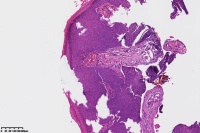

汗孔瘤?

性别

女

年龄

50岁

足底丘疹

汗孔瘤。